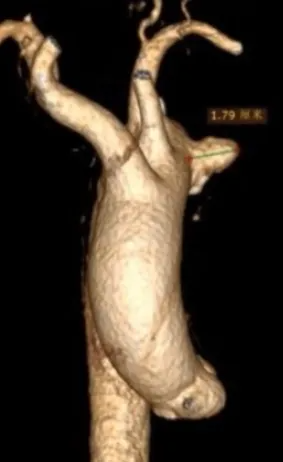

术后恢复情况

患者术后无神经系统定位体征,这意味着手术未对神经系统造成损伤,神经功能保持正常。术后五天复查CTA,可见假性动脉瘤瘤腔内已经完全血栓化,颈总动脉和锁骨下动脉分支血流通畅。出院前复查,LCCA与LSA分支形态良好,血流通畅,无狭窄,主动脉支架封闭效果好,无内漏,治疗效果令人满意。患者身体恢复良好,手术达到了预期治疗目标。

术后5天CTA